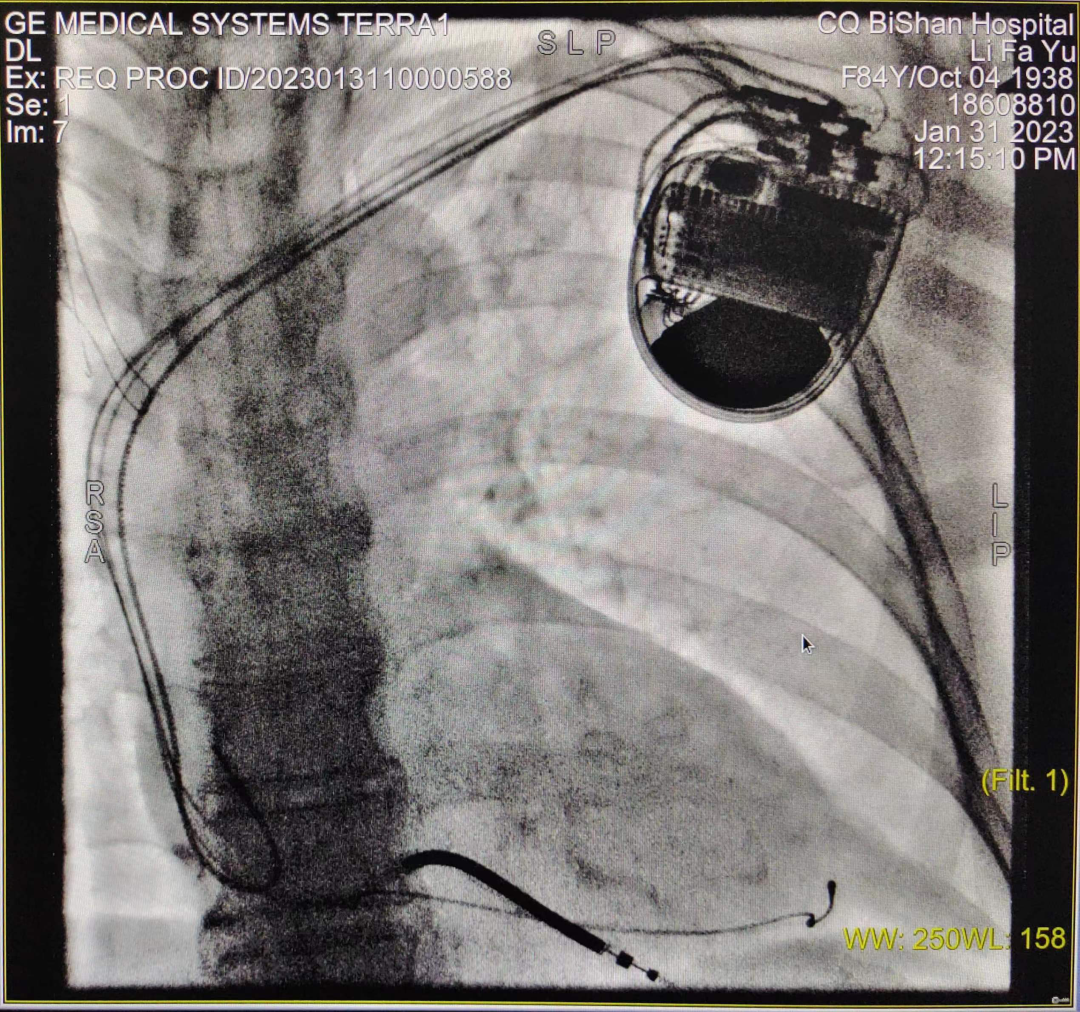

近日,我院心血管內(nèi)科于長青主任帶領(lǐng)的起搏電生理團(tuán)隊(duì)成功為一名慢性頑固性心力衰竭患者,實(shí)施全區(qū)首例CRT-D植入術(shù)(簡稱心臟再同步化除顫器),此項(xiàng)技術(shù)的開展,標(biāo)志著我院心衰器械治療技術(shù)又邁上一個(gè)新的臺(tái)階。

CRT-D植入術(shù)進(jìn)行中

患者為84歲老年女性,20年前反復(fù)出現(xiàn)活動(dòng)后胸悶、心悸,通過間斷服藥癥狀可緩解。本次因勞累、氣促、乏力加重于2023年1月9日入住我院心血管內(nèi)科,完善心臟彩超提示:EF:28%  SV:42ml、左心增大、肺動(dòng)脈收縮壓增高;紐約心功能評(píng)估III級(jí);心電圖提示完全性左束支傳導(dǎo)阻滯、寬QRS(160ms)、動(dòng)態(tài)心電圖提示完全性左束支傳導(dǎo)阻滯、頻發(fā)室性早搏(15353次/24h)、室早呈R-on-T現(xiàn)象、短陣室性心動(dòng)過速。

于長青主任高度重視,結(jié)合患者既往病史、治療史,先后多次組織科室團(tuán)隊(duì)及醫(yī)院MDT團(tuán)隊(duì)討論,并報(bào)請(qǐng)醫(yī)務(wù)科批示,最終決定給該患者安置三腔起搏器,實(shí)施雙心室同步起搏的心臟再同步化治療,改善患者的心力衰竭癥狀??剖移鸩娚韴F(tuán)隊(duì)經(jīng)過充分的術(shù)前準(zhǔn)備,于1月31日成功為患者實(shí)施CRT-D介入手術(shù),手術(shù)過程順利,患者無任何不適,術(shù)后5天即安全出院。術(shù)后心電圖提示:竇性心律,雙心室起搏心律,QRS寬度120-130ms,患者勞累氣促癥狀較前明顯改善。